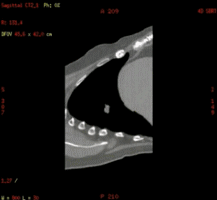

Without MAR

With MAR

在放射治疗科,我可以进行放疗患者CT定位扫描,我可以不依靠第三方厂家,自己做四维呼吸门控扫描,我可以自动去除患者金属伪影,我的老搭档SIM兄弟可以自动勾画正常器官外轮廓,支持在四维CT图像上实时定义修改结构,可以存储为RT DICOM格式发送给TPS。